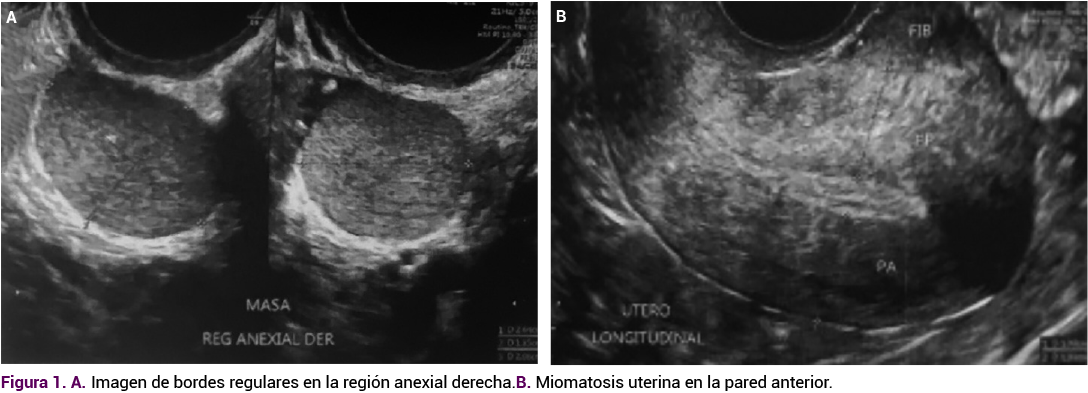

En el ultrasonido endovaginal el útero se encontró aumentado de tamaño debido a la miomatosis uterina intramural y subserosa de medianos elementos, con imagen isoecoica, extraovárica, de 26 x 20 x 18 mm, en la región anexial derecha entre el útero y el ovario ipsilateral, que a la aplicación de Doppler mostró aumento de la vascularidad.

Figura 1. A. Imagen de bordes regulares en la región anexial derecha. B. Miomatosis uterina en la pared anterior.